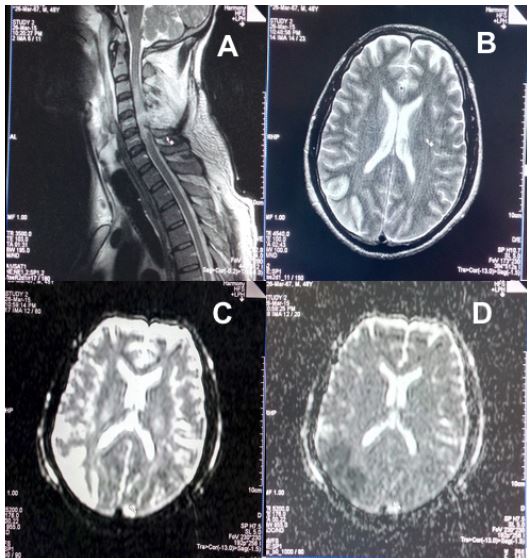

Fig 1 (Case 1: Gunshot wound Face): Non-contrast Computed tomography (NCCT) head revealing (A) Multiple skull fractures including fractures of maxillary antrum, nasal bone, ethmoid and sphenoid; (B and C) Cerebral contusions in bilateral basi-frontal, right anterior and high frontal lobes; (D and E) Contusion in left temporal and occipital lobes; (F) NCCT chest revealing bilateral pleural effusion, basal consolidation and pneumomediastinum.

He was air evacuated on ventilator support to a tertiary care facility on the third day post injury for definitive management of fractured maxilla and palate, right open-globe injury, pharyngeal wall injury and a suspected splinter induced vascular injury on left side of neck. The Glasgow Coma Scale (GCS) was 7/15 with improving revised trauma scores. Noncontrast Computed Tomography (NCCT) of head revealed multiple fractures of skull, maxillary antrum, nasal bone, ethmoid and sphenoid, and cerebral contusions in bilateral basi-frontal, right anterior, high frontal, left temporal and occipital lobes. NCCT of chest revealed bilateral pleural effusion, basal consolidation and pneumomediastinum (Figure 1).NCCT of the cervical spine revealed multiple metallic foreign bodies in the neck with a large hematoma in the left parapharyngeal space. Computed tomography angiography revealed normal carotids. On the fourth day post injury, evacuation of the neck hematoma, re-packing of the oronasal and orbital cavity were performed followed by feeding via tube gastrostomy and jejunostomy. His left eye revealed optic disc hemorrhage.